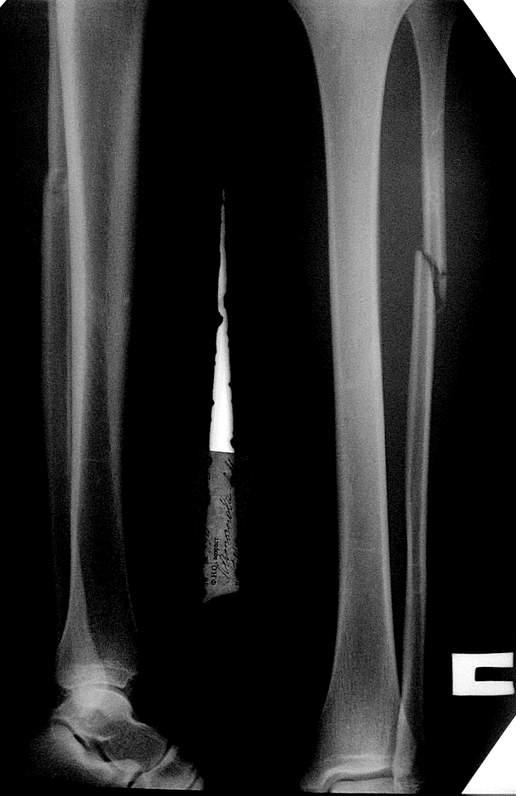

здесь пропускаем повреждение Maisonneuve...

Здесь как раз тот случай, когда рентгеновский снимок скрывает главную проблему. "Ходит, прихрамывая на правую ногу, отмечает боли в правом голеностопном суставе" По описанию клиника типичная для повреждения голонестопного сустава - синдесмоза.

При проксимальных переломах малоберцовой автоматически необходимо подозревать повреждение синдесмоза - Maisonneuve Fracture.

"На западе", как правило, при переломах голеностопа требуются снимки проксимальной части голени.

Описанное в 1840 году Maisonneuve повреждение характеризуется тем, что при фиксированной наружной ротации стопы повреждается передняя фибуло-тибиальная связка, часть синдесмоза, с переломом медиальной лодыжки и без, дальше разрыв продолжается по межкостной мембране и спиральный или косой перелом малоберцовой происходит выше.

Невозможно устранить проблему фиксацией малоберцовой пластиной или другими методами, потому что главная проблема - разрыв межберцовой мембраны, которая находится между костями и внизу в голеностопе в синдесмозе.

Две параллельных шурупа создают условия для сращения мембраны и синдесмоза, 8 недельный срок достаточен, и можно удалить фиксаторы.